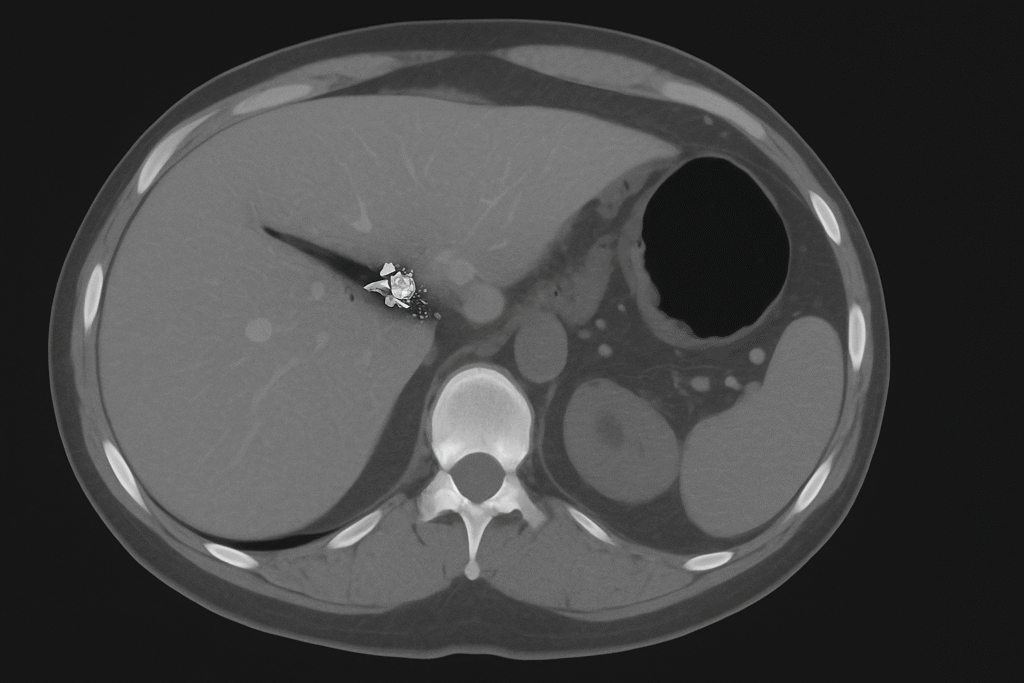

Because the liver isn’t always the only thing bleeding, sometimes air is rushing in where it doesn’t belong. The Trap of Focus Right upper quadrant … Read more